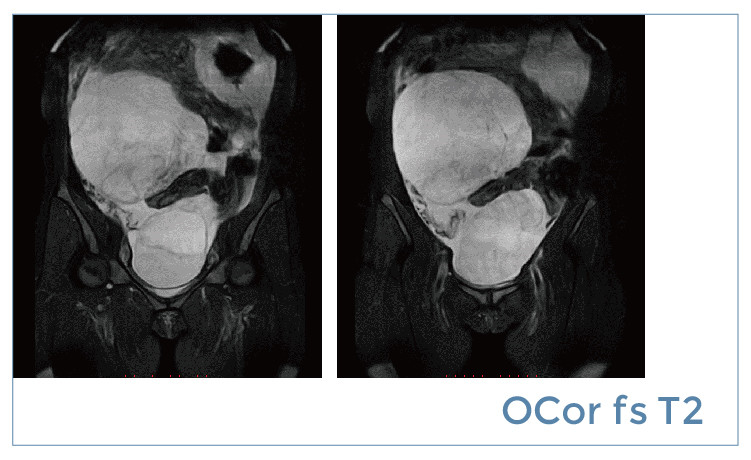

【朗润影像档案】20190419磁共振影像病例结果讨论